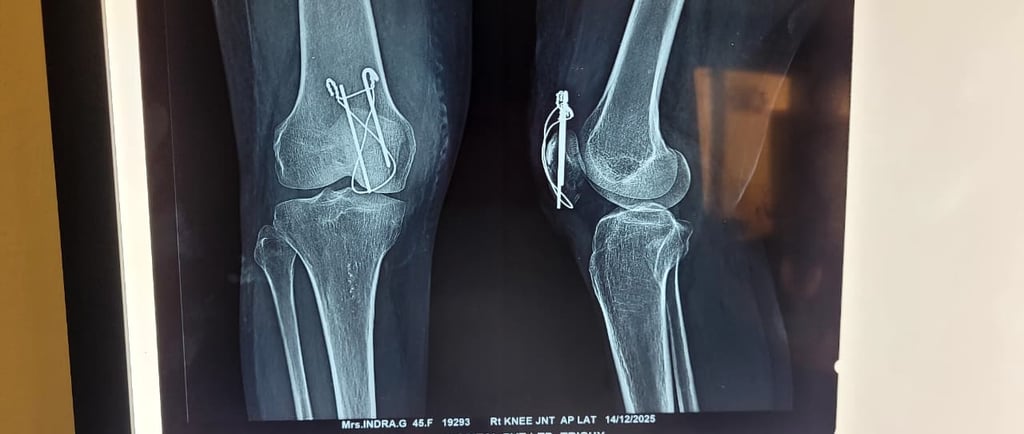

Patella Fracture – Understanding the Injury and Its Treatment

A patella fracture (kneecap fracture) is a common knee injury that usually occurs due to a direct fall on the knee, sports injury, or road traffic accident. The patella plays an important role in the knee extensor mechanism, helping the quadriceps muscle straighten the leg for normal walking and movement.

In some cases, the fracture becomes displaced, meaning the broken bone fragments move apart. A two-part displaced patella fracture disrupts the normal knee function, making it difficult or impossible for the patient to straighten the leg or walk properly.

Such fractures usually require surgical fixation using K-wire and Tension Band Wiring (TBW). This procedure helps to realign the broken fragments, stabilize the bone, and restore the knee’s extensor mechanism, allowing proper healing and recovery.